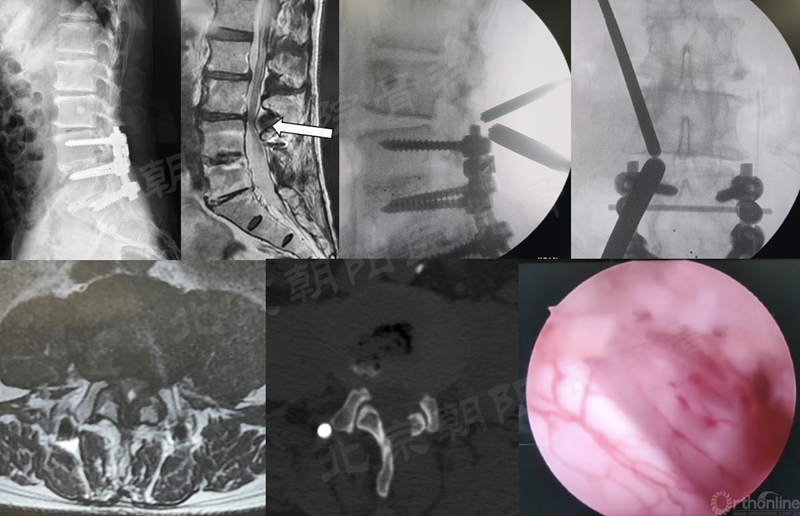

#12例UBE,PLIF术后8年L3/4 ASD。

在经历15例UBE减压手术的学习曲线后,本团队进行了UBE腰椎减压融合术:#16例UBE,L4/5 LSS。

UBE-LIF手术步骤大致按常规开放手术:

1、显露L4椎板下缘-L4/5关节突-L5椎板上缘;

2、Kerrison钳减压L4下关节突(全部去除)-L5椎板上缘-L5上关节内侧缘(尽量靠外)-黄韧带整体切除;

3、硬膜外止血,显露椎间盘,确定椎间隙位置和方向;

4、椎间隙处理:骨刀,髓核钳,终板刮刀,Kerrison钳,电凝,+耐心;

5、自体骨+同种异体骨植骨;

6、可撑开融合器植入(透视定位);

7、检查遗漏的骨块,彻底清除神经周围的致压物;

8、必要时做对侧黄韧带减压;

9、经皮植入椎弓根螺钉,加压固定。

术前MRI和术中定位

椎间隙处理

植入可撑开Cage

术后X线片与CT(矢状面)

术前、术后MRI及CT(轴位)